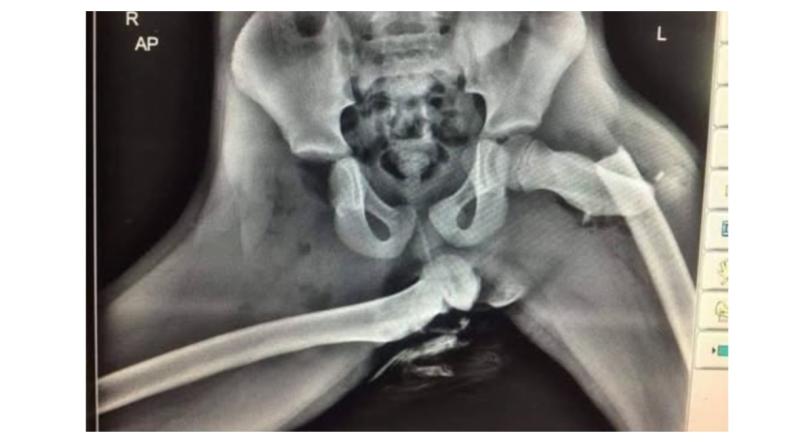

Gardaí urge passengers not to sit this way with an image of an Xray of a passenger in aftermath of a crash

An Garda Síochána have issued a chilling warning to road users, especially passengers about the dangers of sitting with their feet up on the dashboard.

In a post shared to social media, Kilkenny gardaí showed an image shared with them by a Welsh police officer involved in casualty reduction, they said: "It's not a new image but never gets old. It's an Xray of a passenger in a car that had her feet up on the dashboard when a collision occurred."

They continued: "When a collision occurs, it's not the speed does the damage but slowing down. For safety systems to function properly in modern cars, you need to be seated correctly with your approved restraint functioning properly.

"You need to have your seatbelt on correctly, the seat angled correctly, your feet where they should be and all your passengers likewise."

The post concluded: "Save our Paramedics and Medical personnel from seeing sights like this. Save yourself from suffering them."